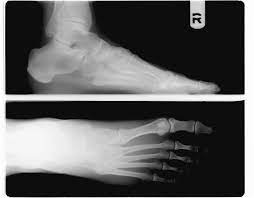

족저근막염은 발바닥을 덮고 있는 근막인 족저근막에 염증이 생겨 발생하는 질환이며, 다음과 같은 증상이 나타날 수 있습니다.

전형적인 증상은 아침에 일어나 처음 발을 디딜 때 느껴지는 심한 통증이 특징적이지만, 모두 같은 증상을 겪는 것은 아니다. 통증은 주로 발꿈치 안쪽에 발생하는 경우가 대부분이고 발뒤꿈치뼈 전내측 종골 결절 부위를 누르면 통증이 발생하기도 한다. 발가락을 발등 쪽으로 구부리면 통증이 심해지기도 한다.